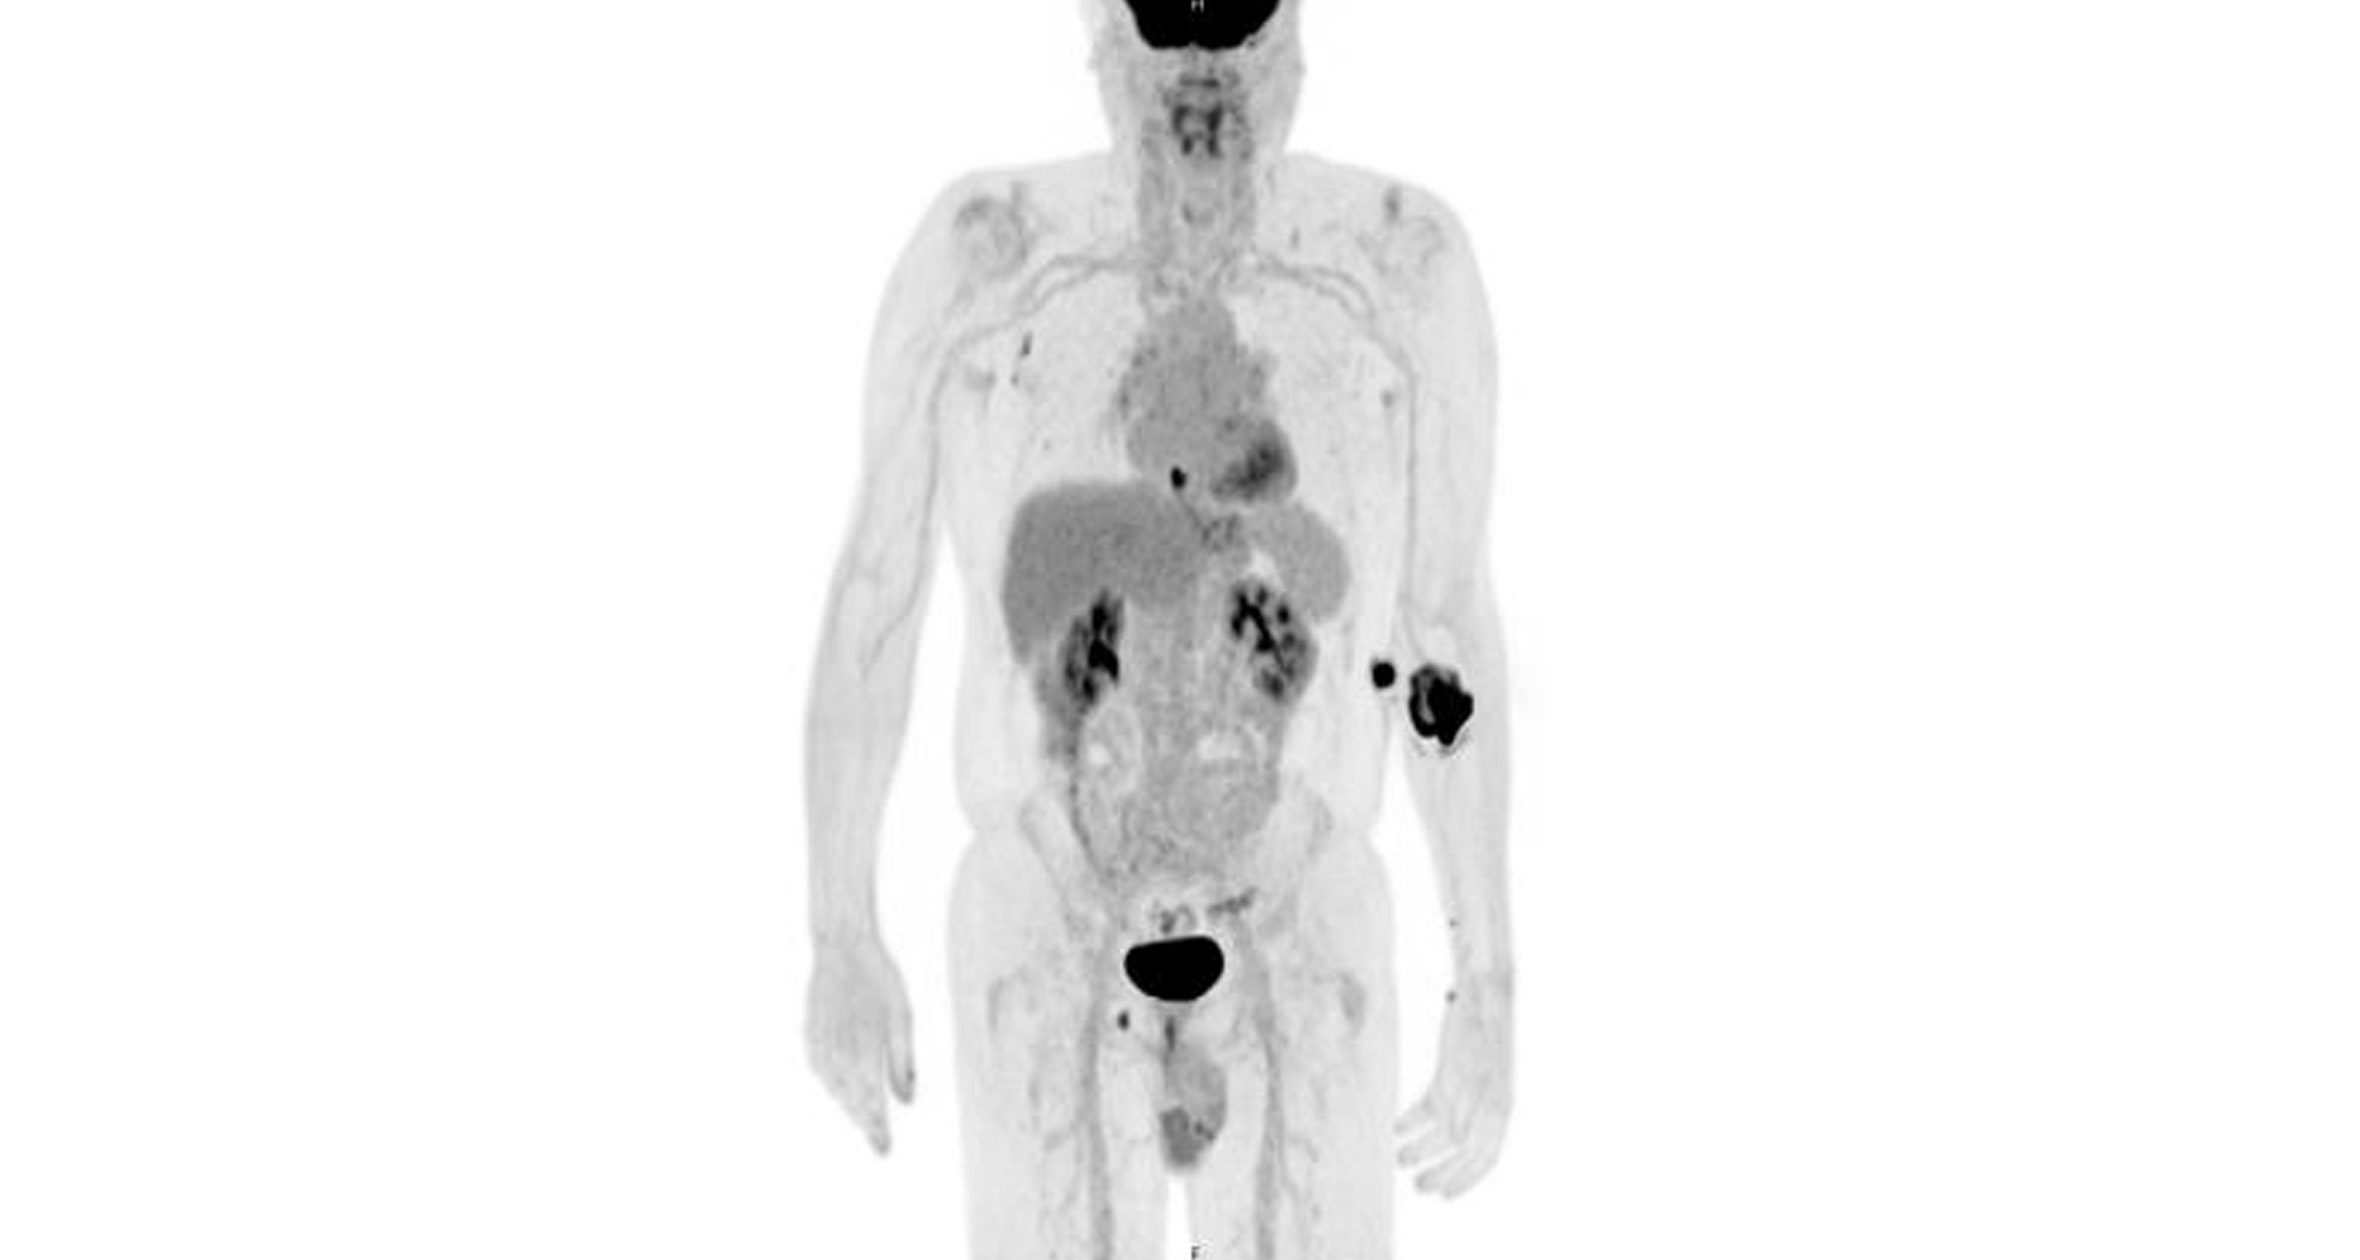

The minimally invasive repair of adult pectus excavatum required cryoablation and three titanium bars, but the patient went home the next day.